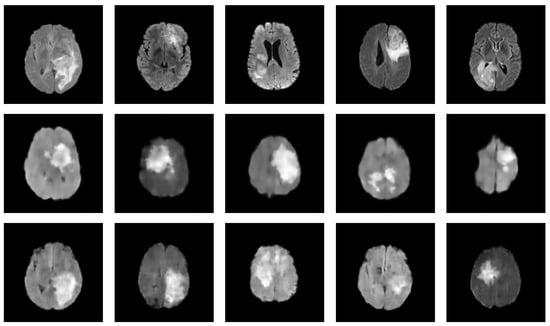

Figure 6.

Figure presenting a comparison between synthesized MRIs generated by a VAE and a Hamiltonian VAE [159]. Both models were trained on a limited training set of 100 images from BraTS2020 Challenge dataset. The first row showcases original images, while the second and third rows present synthesized images generated by the VAE and Hamiltonian VAE, respectively. While the images generated by both models appear slightly fuzzy, the Hamiltonian VAE demonstrates enhanced performance in generating realistic images. This comparison highlights the robustness of the VAE and Hamiltonian VAE for generating new images from a small dataset [158].